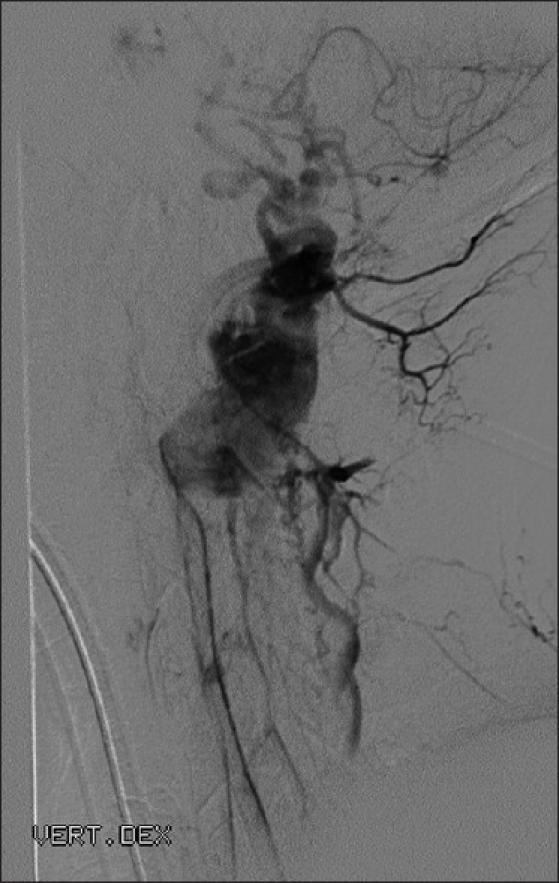

Seventeen patients underwent microsurgical resection of 20 spinal HBs at the Department of Neurosurgery at Helsinki University Central Hospital (HUCH). Thirteen tumors were in the cervical spine, five in thoracic and one patient had two lumbar lesions. MRI tumor showed an associated syrinx in 16 patients (94%). Tumor volume ranged from 27 to 2730 mm(3). Out of 17 patients, 11 (65%) tested positive for VHL in mutation analysis. Five of these patients with tumors ranging from 55 to 720 mm(3) were treated prophylactically.

17例患者在赫尔辛基大学中心医院(HUCH)神经外科接受了20例脊髓HB的显微手术切除。13个肿瘤位于颈椎,5个位于胸椎,1例患者有2个腰椎病变。MRI检查显示16例患者(94%)伴有脊髓空洞症。肿瘤体积为27至2730立方毫米。在17例患者中,11例(65%)在突变分析中VHL检测呈阳性。其中5例肿瘤体积为55至720立方毫米的患者接受了预防性治疗。